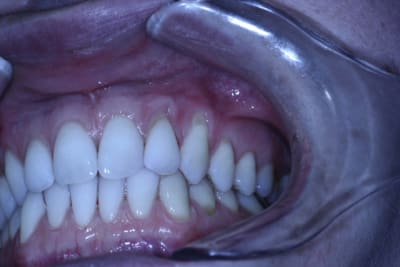

J'hésite sur le choix de la technique.

La patiente est jeune, non fumeuse, aucun problème de santé et très préoccupée par son problème de gencive.

En clair très motivée.

Les récessions sont des Cl I de Miller, donc bon pronostic.

Bon le redimensionnement de la 1è photo est nul, mais ça reste visible, même pour les cancres au fond là-bas.